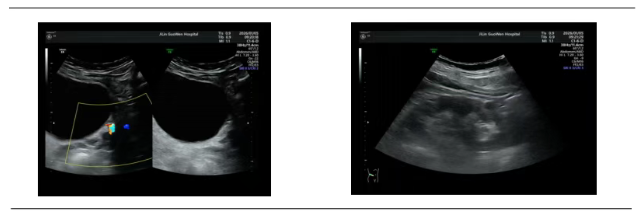

家住附近的李先生(化名),发病时正值午后,左侧腰腹突然传来剧烈绞痛,痛感一路蔓延到小腹,浑身冷汗直流,连路都走不了,甚至出现了尿频、排尿不适的症状。家人紧急送医后,泌尿系彩超明确病因:左侧输尿管下段结石,大小0.9cm,伴有轻微肾积水。

拿到结果的李先生(化名)十分发愁:身边有人结石开刀做手术,恢复期长又遭罪,自己工作繁忙,根本没时间休养;可放任不管,疼痛反复不说,医生告知积水加重会伤肾,进退两难。泌尿外科专家团队仔细评估后,给出了精准方案:患者结石位置、大小完全符合体外冲击波碎石指征,无需开刀手术,无创碎石就能解决问题。